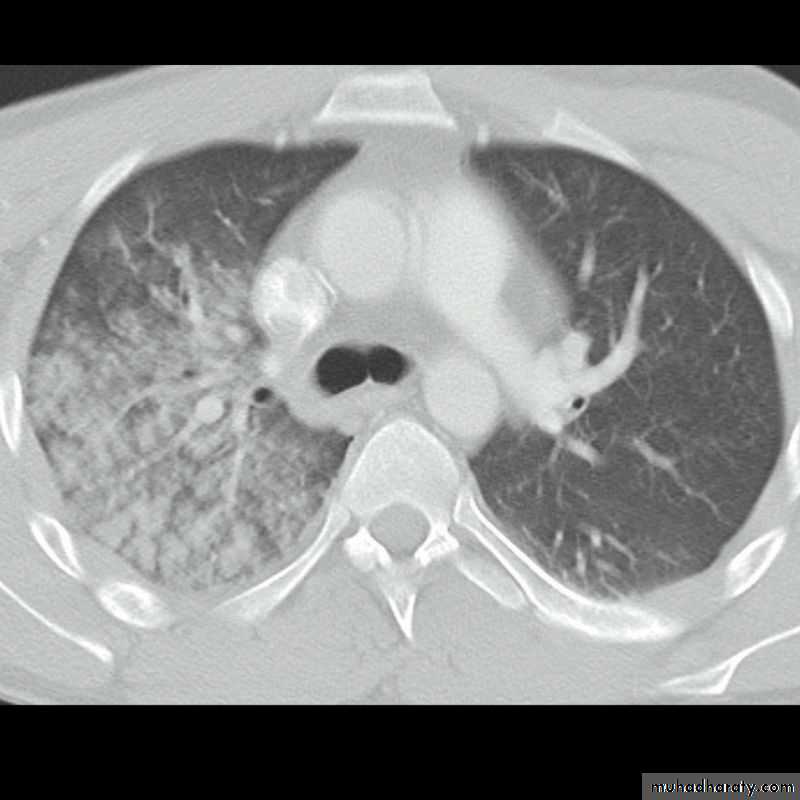

Severe dyspnea with shock